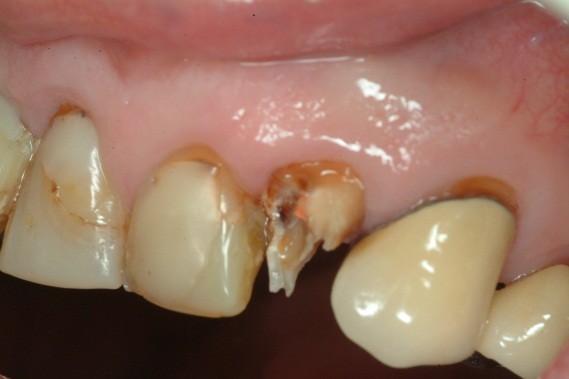

A toothache caused by a broken tooth (tooth fracture) without associated cavity or advanced gum disease. Biting on the area of tooth fracture can cause severe sharp pains. These fractures are usually due to chewing or biting hard objects such as hard candies, pencils, nuts, etc. Sometimes, the fracture can be seen by painting a special dye on the cracked tooth. Treatment usually is to protect the tooth with a crown. However, if placing a crown does not relieve pain symptoms, a root canal procedure may be necessary.